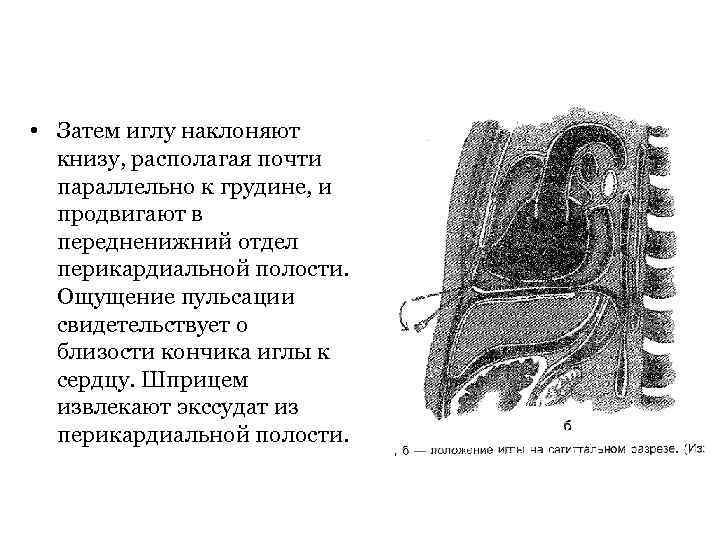

• Затем иглу наклоняют книзу, располагая почти параллельно к грудине, и продвигают в передненижний отдел перикардиальной полости. Ощущение пульсации свидетельствует о близости кончика иглы к сердцу. Шприцем извлекают экссудат из перикардиальной полости.

• Затем иглу наклоняют книзу, располагая почти параллельно к грудине, и продвигают в передненижний отдел перикардиальной полости. Ощущение пульсации свидетельствует о близости кончика иглы к сердцу. Шприцем извлекают экссудат из перикардиальной полости.